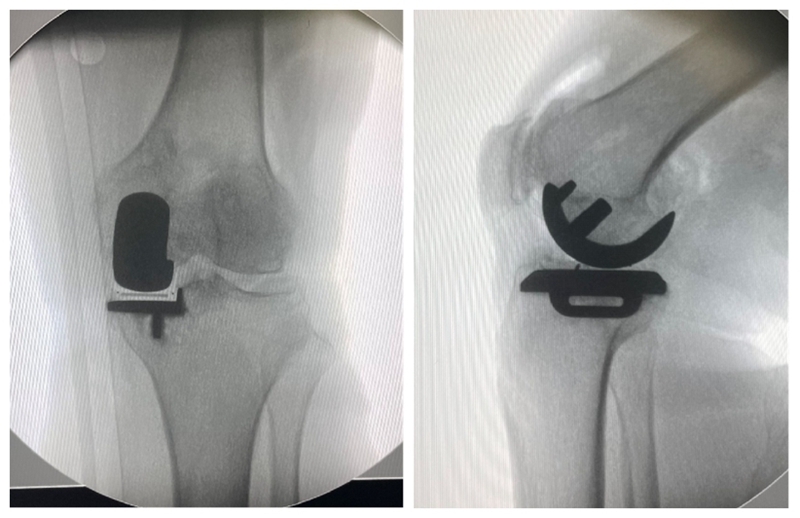

高龄患者内侧单髁置换术

术前

术后检查

对于80岁以上的高龄膝关节骨关节炎患者,准确手术评估、恰当围术期处理、选择微创UKA,不仅有效,而且安全可行。与TKA相比,高龄患者采用UKA治疗不仅有效,还具有并发症少、输血率低、住院时间短、恢复快等特点。但是,高龄膝关节骨关节炎患者通常合并较多内科疾病,围术期科学管理尤为重要。应注意以下几点:术前高血压患者血压应控制在160/90 mm Hg以内;糖尿病患者血糖应控制在10.0 mmol/L以内,尿糖(+++);冠状动脉粥样性硬化病患者适当给予扩张冠脉及营养心肌治疗,超声心动图示左心室射血分数超过 50%以上;心律失常患者完善24 h动态心律检测,必要时请心内科协助诊治;慢性肺部疾病患者肺功能最大通气量超过 60%以上。另外,术前需关注贫血及低蛋白血症情况,必要时给予输血或补充白蛋白治疗。熟练操作、严格微创、减少手术时间及术中出血是手术成功关键。